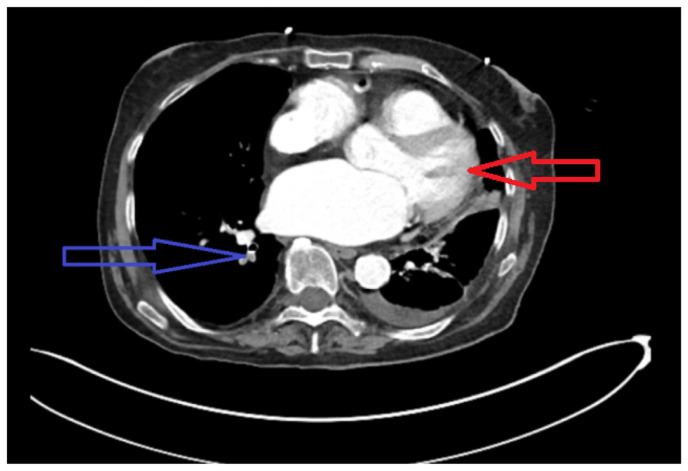

Pancreatic carcinoma has remained one of the leading causes of cancer-related mortality worldwide. Cancer originating in the head of pancreas is often detected early in the disease due to biliary obstruction resulting in jaundice. In contrast, cancer of the pancreatic body and tail remains indolent, presenting late with significantly increased tumor burden and distant metastasis. Unfortunately, a single laboratory screening study is neither sensitive nor specific for early detection of pancreatic cancer. In this report, we present a patient with longstanding diabetes incidentally detected to have pancreatic tail carcinoma while presenting with pulmonary embolism, emphasizing the need for pancreatic cancer screening studies in population with longstanding diabetes.